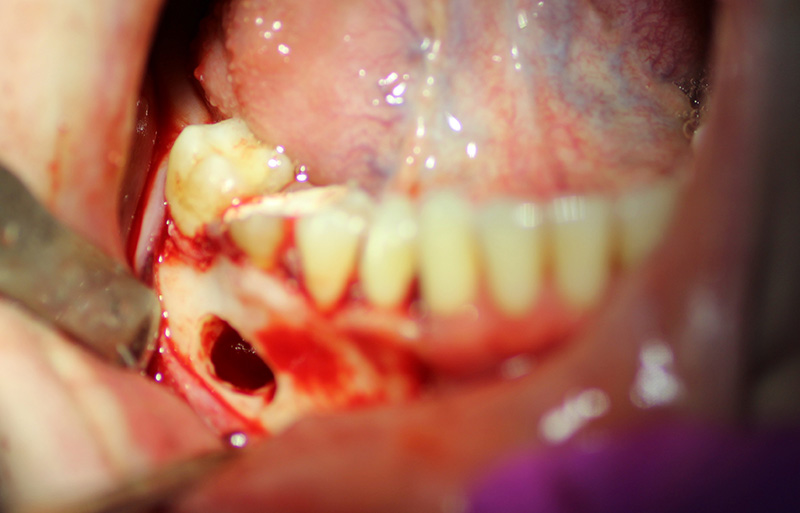

The patient underwent an operation of apicotomy (resection of the apex of the tooth root) and removed the cyst.